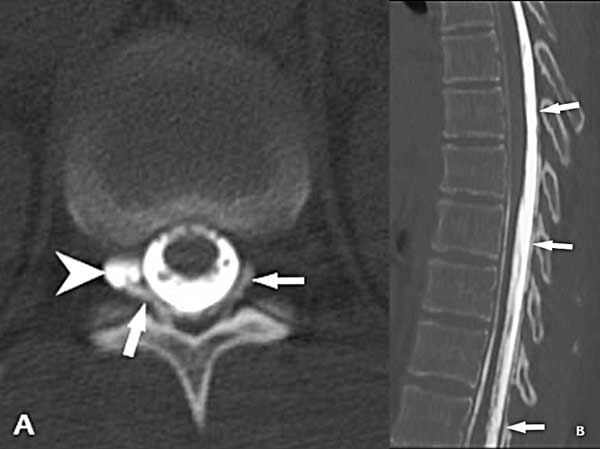

En julio del 2023 se efectuó una inyección de contraste yodado (iopamidol 370) por vía intratecal lumbar a razón de 1 cm3/segundo en la camilla del tomógrafo (GE light speed de 16 hileras) en decúbito ventral. Esto ocasionó una importante cefalea que fue cediendo en los minutos siguientes. Inmediatamente concluida la inyección, se realizó la adquisición en modo helicoidal de la columna lumbar y posteriormente se fueron obteniendo secuencias de la columna dorsal siguiendo el ascenso del contraste. A nivel T11/12 se identificó un quiste de la vaina radicular derecha que mostraba extravasación del medio de contraste al espacio extradural en dirección cefálica hasta aproximadamente T7 (Figura 3).

Figura 3. Mielo-TC. A) Corte axial a nivel T12/L1 que muestra el llenado del quiste radicular derecho (punta de flecha) y la salida del medio de contraste al espacio extradural (flechas). B) Reconstrucción sagital de la columna dorsal que muestra el ascenso del medio de contraste por fuera de la duramadre dorsal hasta el nivel T7 (flechas).